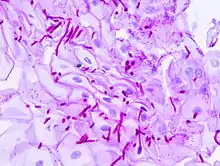

Periodic acid–Schiff (PAS) is a staining method used to detect polysaccharides such as glycogen, and mucosubstances such as glycoproteins, glycolipids and mucins in tissues. The reaction of periodic acid oxidizes the vicinal diols in these sugars, usually breaking up the bond between two adjacent carbons not involved in the glycosidic linkage or ring closure in the ring of the monosaccharide units that are parts of the long polysaccharides, and creating a pair of aldehydes at the two free tips of each broken monosaccharide ring. The oxidation condition has to be sufficiently regulated so as to not oxidize the aldehydes further. These aldehydes then react with the Schiff reagent to give a purple-magenta color. A suitable basic stain is often used as a counterstain.

PAS staining is mainly used for staining structures containing a high proportion of carbohydrate macromolecules (glycogen, glycoprotein, proteoglycans), typically found in e.g. connective tissues, mucus, the glycocalyx, and basal laminae.

- Fungal infection, the cell walls of fungi stain magenta; this only works on living fungi. In contrast, Grocott's methenamine silver stain (GMS) will stain both living and dead fungal organisms.